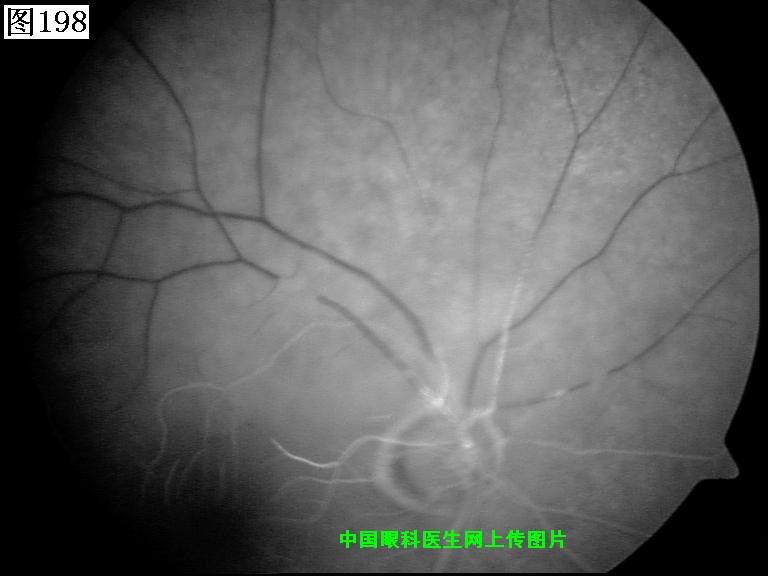

197 198 199 200